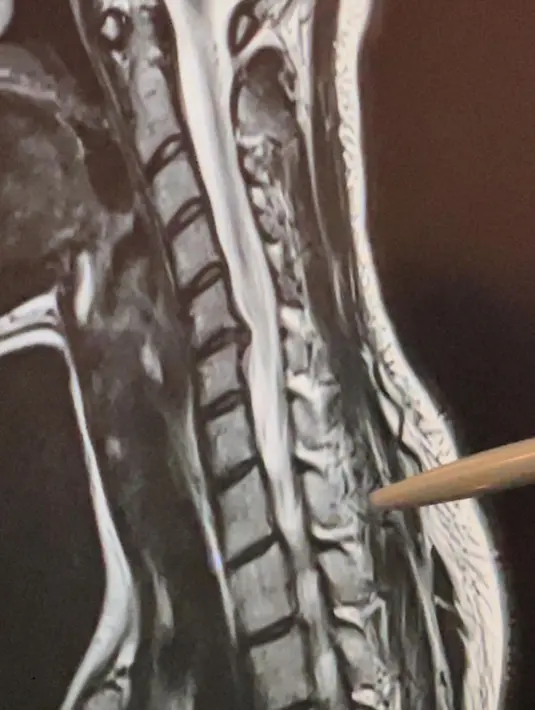

Penyanyi muda, Sheryl Sheinafia selesai menjalani perawatan usai dinyatakan mengalami syaraf kejepit. Membagikan tiga foto, potret pertama selfie di salah satu ruangan rumah sakit, potret kedua membagi hasil rontgen, dan ketiga tampak lehernya di balut dengan penyangga.(Instagram/sherylsheinafia)